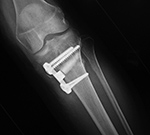

Right tibia bone graft

43 year-old man with comminuted right tibia and fibula fractures as well as extensive bone loss and soft tissue injury. A tibial intramedullary nail with proximal and distal locking screws is present as well as multiple rounded bony allografts. There are also large skin staples.